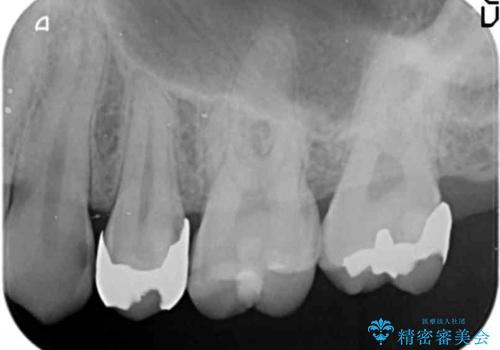

奥歯の詰め物のやりかえ セラミックインレー、ゴールドインレー

- 上の奥歯の詰め物が合っていないため、やりかえを行いました。

- 20万円 内訳 左上56:emaxインレー7万円x2 、左上7:PGAインレー6万円 (税別)費用は治療当時の料金となります

上の一番奥の歯は、一番目立たない場所なので(他人から見えない)、ゴールドインレーでも目立ちません。

セラミックインレーでは割れやすい大きさの虫歯または、歯が薄くなって被せなければいけないような場合でも、金属(ゴールド)は耐久性があり、クラウン(被せ物)にしなくて済みます。